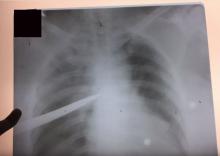

Patient 1: A male patient was assaulted with a broken glass bottle in a bar fight. On examination, he had a wound in the left parasternal area involving the third and fourth intercostal space. The left mid lung was visible through the wound. The trauma ward performed a left tube thoracostomy, which drained 1,000 ml of blood. The patient was then taken for surgical chest exploration. An injury to the left internal mammary artery was ligated and a lung defect was sutured.

Patient 2: A male patient was assaulted with a screwdriver in a street fight and presented with penetrating chest trauma around the xiphisternum. The patient also presented with features of cardiac tamponade. He underwent urgent echocardiography and was taken for surgical chest exploration. The right ventricle was sutured with pledgeted polypropylene.

Patient 3: A female patient was assaulted with a kitchen knife. The wound was located in her right thorax. Surgical exploration was conducted via a right thoracotomy. The knife was removed and the lung defects were sutured.